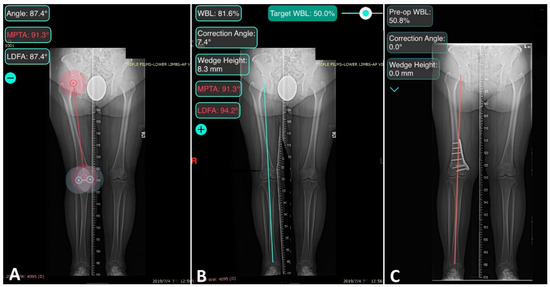

| WBL ratio (%) | 78.7 ± 12.0 | 48.7 ± 2.9 (<0.001) * | 48.1 ± 3.8 (0.44) |

| HKA (°) | 9.3 ± 2.8 | −0.5 ± 1.1 (<0.001) * | −0.3 ± 1.4 (0.58) |

| LDFA (°) | 83.6 ± 1.9 | 91.4 ± 3.5 (<0.001) * | 90.8 ± 3.7 (0.32) |